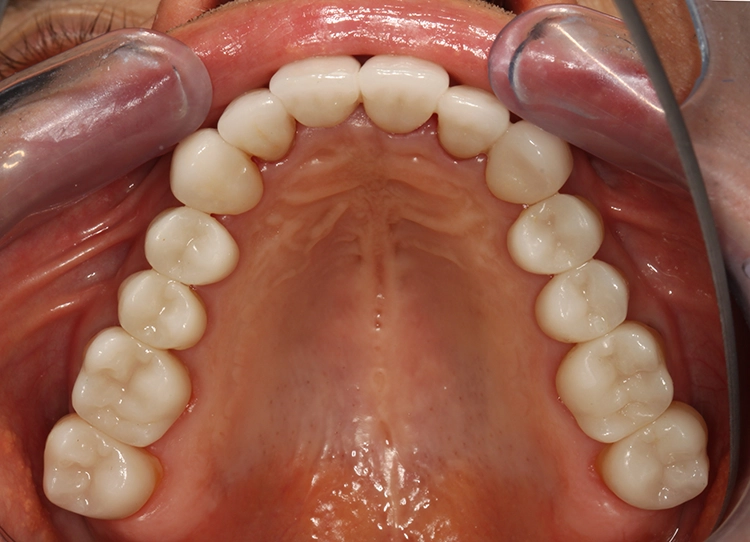

Egger/Wermuth/GrevenRote Ästhetik: Im Ober- und Unterkiefer zeigten sich generalisiert ausgedehnte Rezessionen mit bis zu 8 mm Attachmentverlust vor allem im Bereich der Eckzähne (Miller-Klasse III; Rezessionstyp [RT] 2 [69]. Das Band an keratinisierter Schleimhaut ist durchgehend vorhanden. Die Breite variiert im Eckzahnbereich von 1 mm bis zu 2 mm im Bereich der Unterkieferfrontzähne, der Prämolaren und Molaren (Abb. 1). Die fazialen Rezessionen sind mit approximalem röntgenologischem Attachmentverlust im koronalen Wurzeldrittel (Abb. 2) und Papillenverlust im Bereich zwischen den Kontaktpunkten und der approximalen Schmelz-Zement-Grenze assoziiert (Abb. 1). Der Patient verfügt über eine schmal geformte Oberlippe. Die Lachlinie verläuft mittelhoch (Abb. 3).

Egger/Wermuth/GrevenWeiße Ästhetik: Die Oberkieferfront empfindet der Patient als ausreichend lang. Das entspannte Lächeln zeigt 1/3 der Frontzahnlänge. Der Schneidekantenverlauf folgt der Konkavität der Unterlippe (berührungsaktives Verhältnis). Die oval imponierende Zahnform der Oberkieferfrontzähne erachtete der Patienten als harmonisch. Sie soll bei der Neuversorgung beibehalten werden (Abb. 3). Im Oberkiefer erscheint der Zahnbogen parabolisch mit Versatz im Bereich 11/21. Die Oberkieferfront steht labial (Klasse II/1).

Parodontale Gesundheit bei Attachmentverlust, Bruxismus, Erosion. Abbildung 1 sowie 6 bis 9 zeigen den Anfangsbefund als intraoralen Fotostatus.*